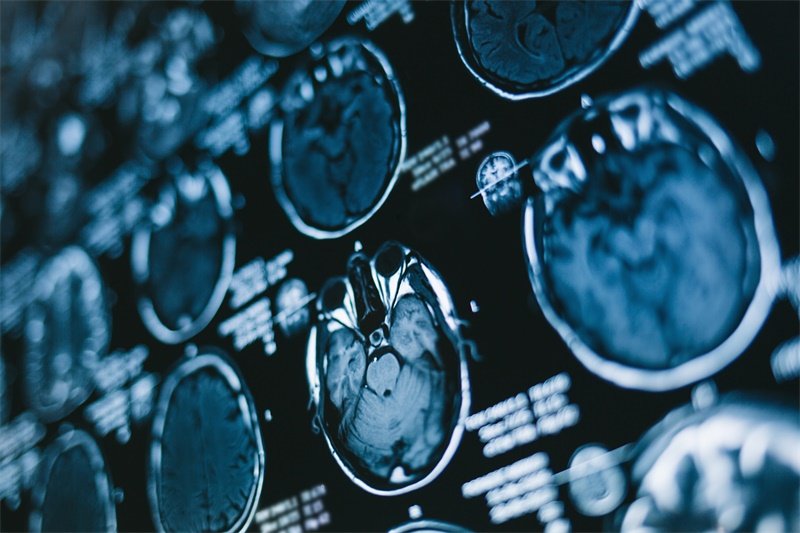

在手术之前,患者需要经过详细的评估,包括影像学检查和实验室测试。这将帮助神经外科医生制定最佳的手术方案。